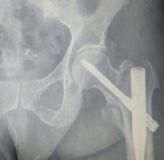

2. Comminuted extracapsular fracture of the left hip in a 69-year-old female.

Treatment: Nailing with a proximal femoral nail

I. Before surgery II. Post-surgery, x-ray showing the proximal part of the nail and the reduction of the fracture III. Post-surgery, x ray showing the distal part of the nail